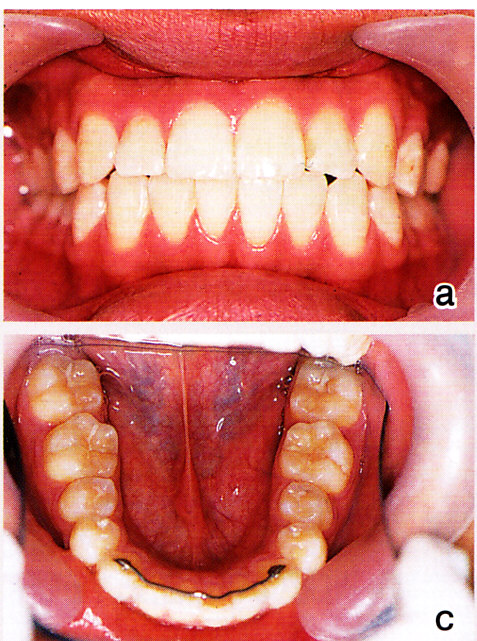

図15 a~c:18歳 下顎前歯に少し乱れが出ているが、臼歯のアップライトが不十分なためと思われる